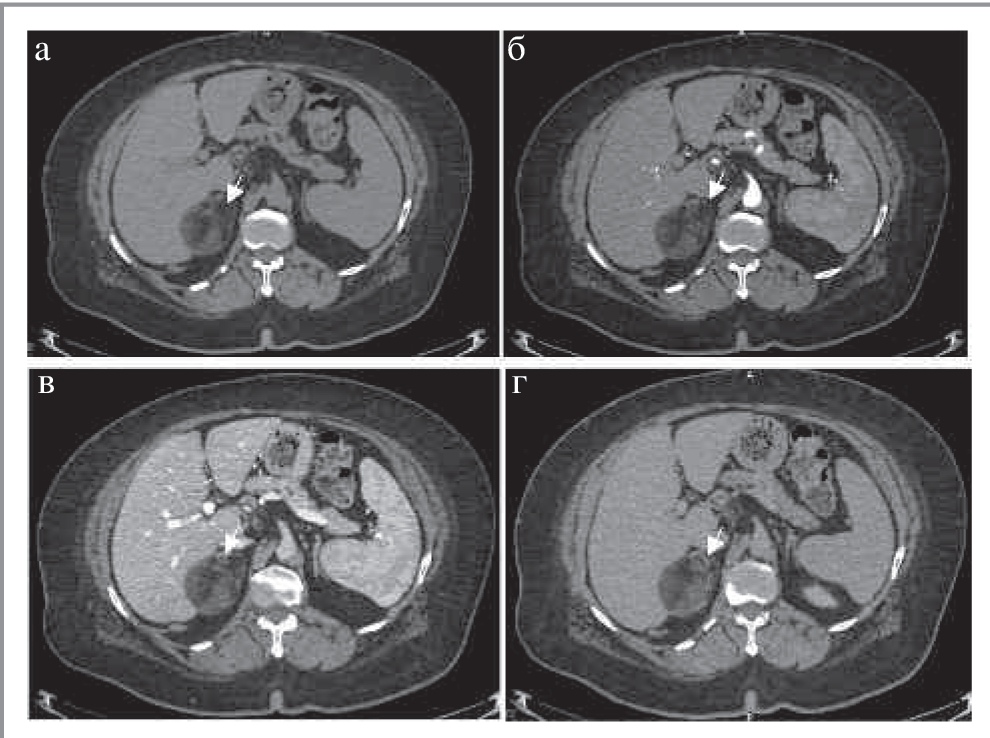

КТ-картина феохромоцитом имеет различные признаки. Размер может варьировать от 1,2 до 15 см, в среднем около 5 см. Небольшие образования чаще однородны, в то время как более крупные часто неоднородны с участками жидкостной плотности (зонами некроза), зонами кровоизлияний, внутренними перегородками, а также обызвествлениями. Большинство опухолей интенсивно накапливает контрастный препарат в АФ с последующим умеренным его вымыванием к ОФ. Контуры образования, как правило, четкие, ровные за счет наличия капсулы (рис. 6). В редких случаях феохромоцитомы могут иметь включения макроструктурного жира, что также характерно и для миелолипом [16].

Рис. 6. МСКТ, аксиальная проекция: а – НФ; б – АФ; в – ВФ; г – ОФ. Параганглиома (стрелка).

Озлокачествление опухоли наблюдается в 11% случаев у спорадических феохромоцитом и в 35% случаев наследственных феохромоцитом [19]. Выявление метастазов (чаще в костях, лимфатических узлах, легких и печени) подтверждает озлокачествление образования. Следует отметить, что, несмотря на то, что выраженное вымывание контрастного препарата для феохромоцитом нехарактерно, в редких случаях они могут иметь характеристики вымывания, аналогичные аденомам (APW более 60% и RPW более 40%), что затрудняет установку диагноза [16].